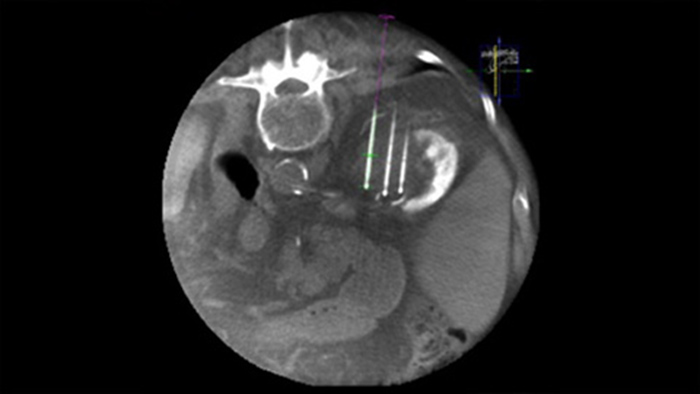

La ablación percutánea (radiofrecuencia, microondas y crioablación) es un tratamiento mínimamente invasivo bien establecido para los tumores de riñón, hígado, pulmón y hueso. Es fundamental definir los límites del tumor y decidir el número óptimo de agujas y la correspondiente trayectoria de estas para poder realizar un tratamiento completo del tumor y no causar daños en el tejido circundante. Navegar con precisión con baja dosis hasta la lesión de interés sin reposicionar la aguja aumenta las posibilidades de éxito y reduce el riesgo de complicaciones de las biopsias o ablaciones. La confirmación del punto final del tratamiento de ablación puede realizarse con imágenes en 3D mientras el paciente sigue en la mesa.

SmartCT Soft Tissue ofrece una técnica de adquisición mediante TC de haz cónico (CBCT) aumentada con guía paso a paso, visualización 3D avanzada y herramientas de medición; todo accesible en el módulo de pantalla táctil desde la mesa.

XperGuide proporciona una guía de imagen en vivo de alta precisión de cada aguja a una posición determinada mediante la superposición de trayectorias preplanificadas con imágenes fluoroscópicas.3